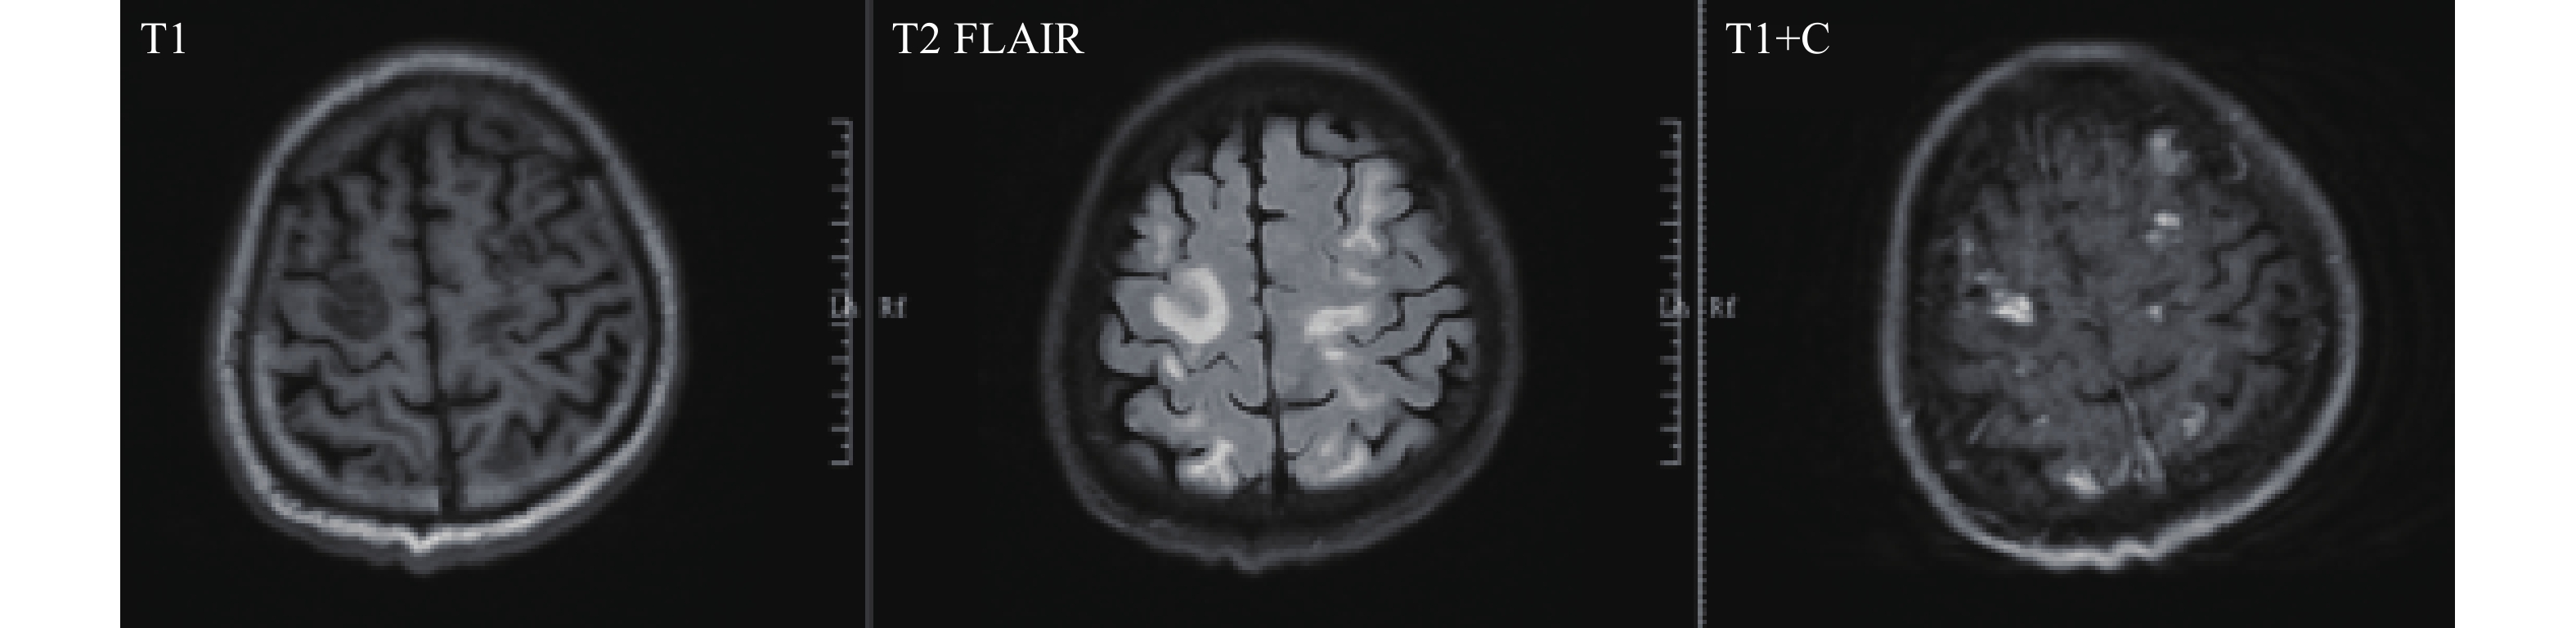

Notably, the patient did not present with typical schistosomiasis symptoms such as fever, abdominal pain, diarrhea, or hepatosplenomegaly. Instead, central nervous system manifestations emerged in April 2025, including limb weakness, slowed reaction time, memory impairment, and loss of independent ambulation. Magnetic resonance imaging revealed extensive FLAIR hyperintensities throughout the bilateral frontal, parietal, temporal, and occipital lobes, with additional involvement of the brainstem and cerebellum. Hemosiderin deposition was noted in the bilateral frontal, parietal, and occipital lobes and the left cerebellar hemisphere. Hypointensity were also observed in the bilateral globus pallidus, suggesting mineral deposition or calcification (Figure 1). Central nervous system lesions resulting from ectopic egg migration can manifest without the more common hepatointestinal symptoms, potentially complicating clinical suspicion of schistosomiasis.

Figure 1.MRI findings reveal multiple symmetrical abnormal signals in the bilateral frontal, parietal, temporal, and occipital lobes, as well as the periventricular regions of the bilateral lateral ventricles.

Abbreviation: MRI=magnetic resonance imaging.Routine blood testing demonstrated marked eosinophilia, with both the percentage (25.0%) and absolute count (3.30×109/L) exceeding normal reference ranges. HTS analysis of blood samples identified four sequences of S. mansoni. Fecal examination employed three methods: automated routine analysis, the egg-hatching method following nylon mesh bag concentration, and the modified Kato-Katz thick smear technique. Automated stool analysis failed to detect any eggs, and the egg-hatching method revealed no miracidia. Using the Kato-Katz technique, examination of three fecal smears yielded no S. mansoni eggs; however, continued testing of an additional seven smears (10 total) identified a single egg (Figure 2). These combined findings provided definitive etiological evidence for diagnosis.